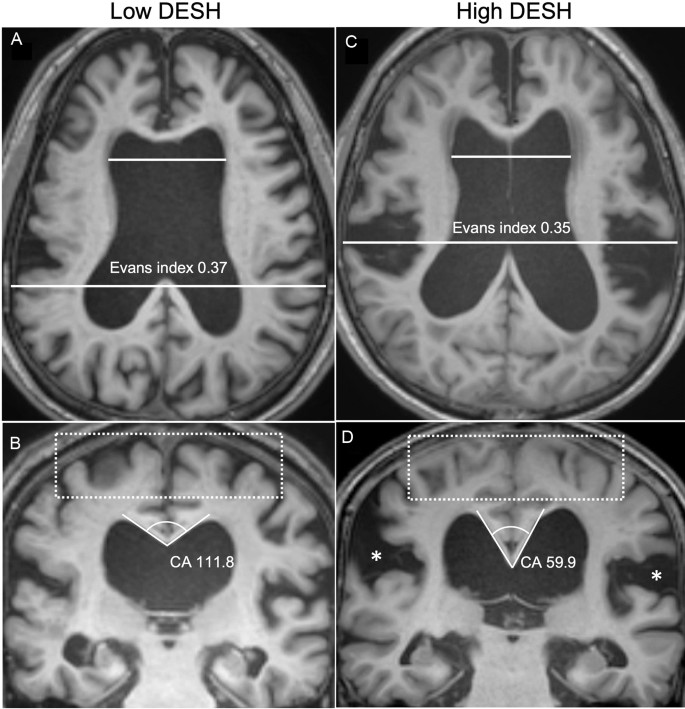

Patients with iNPH were divided into two subgroups, high DESH (DESH scale ≥ 7, n = 19) vs low DESH (DESH scale ≤ 6, n = 14), by the average value (6.73) of the DESH scale (Fig. 1). There was no significant difference in demographics, risk factors, cognitive scores, and iNPHGS between the high- and low-DESH groups (Table 1). The CSF tap test was performed in 10 and 16 patients in the low- and high-DESH groups, respectively. Based on the criterion of at least 10% improvement in gait velocity in the timed up and go evaluation15, 70% (low-DESH group) and 62.5% (high-DESH group) patients showed improvement, respectively. Improvements of 3 or more points in cognitive function assessed by Mini-Mental State Examination (MMSE) before and after the CSF tap test were observed in approximately 20 and 18.8%, respectively16. Shunt surgery was performed in only 8 of 33 patients, all but one of whom were in the high-DESH group. Two patients required reoperation due to shunt malfunction, but all patients had improved postoperative subjective symptoms and iNPHGS (Table 1). Due to the retrospective nature of the study, objective quantitative measures were not consistently collected before and after surgery. DTI was also not collected postoperatively.

Representative MR images of the high-DESH and low-DESH group. MR coronal and axial images of representative patients in the low-DESH (a,b) and high-DESH (c,d) groups. In the low-DESH patient, the Evans index is increased to 0.37 (grade 2, panel a), the sylvian fissures are slightly enlarged (grade 1), but no tight high convexity is observed, (white-dotted rectangle) and the callosal angle is 111.8°, which is above 90° (panel b). This patient has a DESH score of 3. In the high-DESH patient, the Evans index is increased to 0.35 (grade 2, panel c), similar to the low-DESH patient, but in addition, the sylvian fissure is markedly dilated bilaterally (grade 2, white asterisks), tight convexity is seen (grade 2, white-dotted rectangle), and the callosal angle is less than 90° at 59.9° (grade 2). This patient also has focal sulcal dilatation (grade 1, not shown), resulting in a DESH score of 9. DESH disproportionately enlarged subarachnoid space hydrocephalus, CA callosal angle.

The DESH score is composed of the following five items, each scored from 0 to 2 (maximum total score 10): ventriculomegaly, dilated sylvian fissures, tight high convexity, acute callosal angle, and focal sulcal dilation3 (Supplementary Table S2). Ventriculomegaly was assessed using the Evans' index (EI), the ratio of the maximum width of the frontal horns to the maximum transverse diameter of the inner table in the same section45, measured and calculated manually from the axial T1–weighted MRI. Then, it was graded as follows: 0, EI < 0.3; 1, 0.3 ≤ EI < 0.35; or 2, EI ≥ 0.35. Dilated Sylvian fissures and tight high convexity were evaluated on coronal images and graded as follows, respectively: 0, normal; 1, unilateral dilation; or 2, bilateral dilation; and 0, normal; 1, slight compression; 2, definitive compression46,47. The callosal angle (CA) measured on a coronal image is the angle between the lateral ventricle and the posterior commissure and is perpendicular to the anterior–posterior commissure plane48,49. CA was graded as follows: 0, CA ≥ 100°; 1, 90 ≤ CA < 100°; 2, CA < 90°. Sulcal dilation was graded as follows: 0, no sulci; 1, some sulci present; or 2, many sulci present. These imaging features of DESH were visually assessed by three neurologists (S Lee, S Jo, and H-J Kim) blind to clinical data. The intraclass correlation coefficient (ICC) for inter-rater reliability of DESH scoring was 0.814.